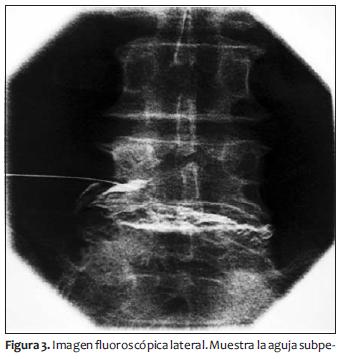

Al inyectar 0,5 ml de contraste se observó la habitual imagen periradicular de L4 acompañada de una imagen intradiscal. Al inyectar otros 0,5 ml de contraste en tiempo real se observó el llenado del disco L4-L5 acompañado de dolor lumbar transitorio (figuras 3 y 4).